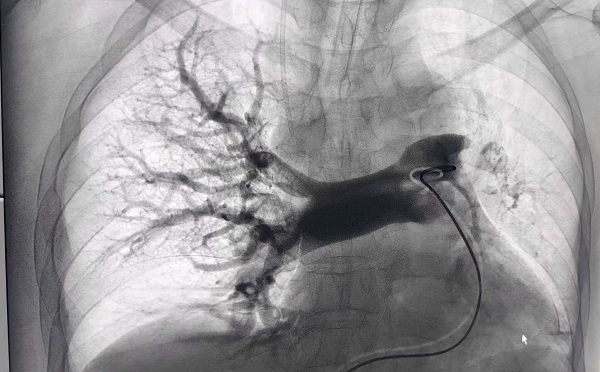

术中见左肺动脉主干未见显影,右肺动脉大分支多发充盈缺损

术后造影见右肺动脉大分支及主干充盈缺损消失,左肺动脉主干显影良好。